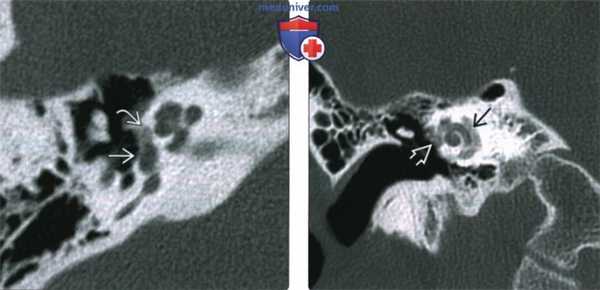

(Слева) При аксиальной КТ правой височной кости определяется бляшка смешанной структуры (со склеротическим и «прозрачным» компонентами) спереди от овального окна с вовлечением щели перед окном. Склеротическая часть бляшки при фенестральном отосклерозе обусловлена процессом заживления, рентгенопрозрачная часть - активным процессом.

(Справа) При аксиальной КТ левой височной кости визуализируется отоспонгиозная бляшка смешанной (склеротической и рентгено-негативной) структуры, приводящая к обструкции круглого окна. Отосклероз предрасполагает к невозможности протезирования стремечка и затрудняет кохлеарную имплантацию.